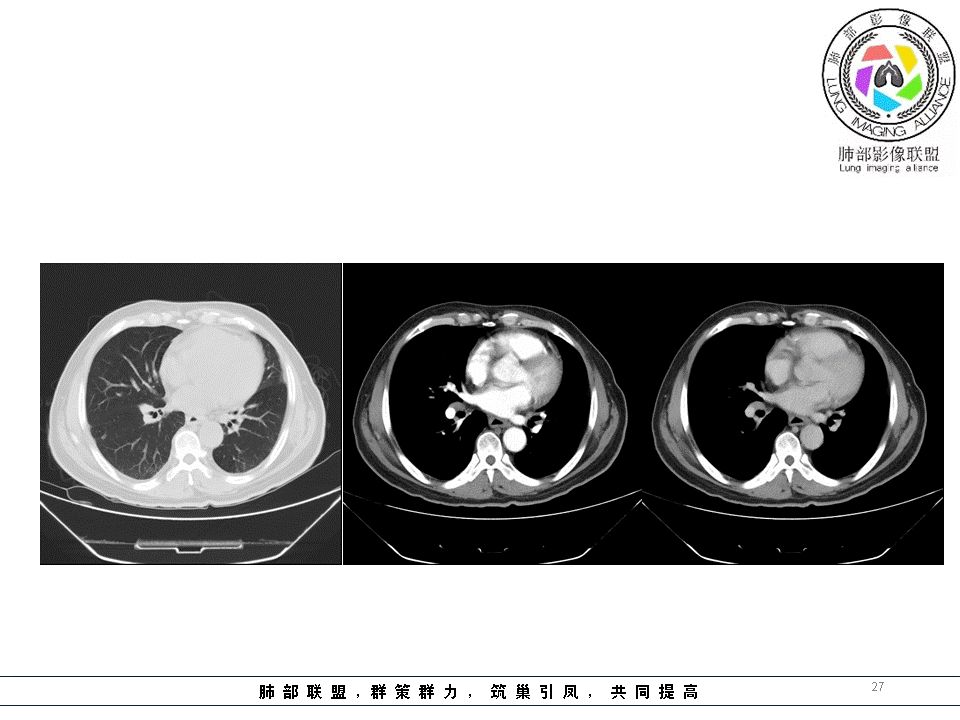

南边:临床:老年男性,病史偏长,2月。临床有通气功能障碍。

我们看影像,肺内有一些小斑点状高密度影,部分区域有气体潴留:

南边:我们现在影像上看的,也就是肺部小斑点,这些斑点,有些地方有气道储留的一个特点。

南边:但是我们看纵隔就多发的肿大淋巴结,部分融合成团。

南边:而且这些淋巴结,有些直接主要是压迫支气管壁,但是有些是突入到支气管腔内的。可惜我截的图发不上来。就左上舌段,支气管壁明显的增厚。有些明显腔内突的一个结节的,但是远的没有阻塞的特点。南边:增强以后呢,这个病灶明显强化,部分的似乎有环形强化的迹象,但不是很典型。

我们看这个主支气管的层面,主支气管明显受压,有变形的,但是软骨是没有突破的。

南边:那也就是说,这个纵隔淋巴结,它是没有影响到我们主支气管内部去的,周围有,可惜的膜部的增厚,我总心里不踏实,后面因为食道贴在一起啦。 因此这些淋巴结在主支气管层面是没有影响的。

这个区域明显就是一个支气管本身有问题。

但是有一个地方有问题的,左侧的上叶的下舌段这个区域:

左上叶舌段这个气管腔内是有东西凸进去。

首先弥漫性的,支气管壁是一个问题,然后有病灶凸向腔内,那又是一个问题,我有两种想法。

1、支气管壁本身有问题,2周围淋巴结侵犯支气管壁

结果:肺腺癌并纵膈淋巴结转移